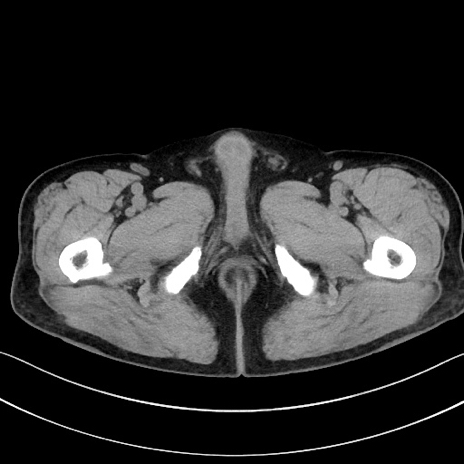

症例15(横断像)

【症例】70歳代男性

【主訴】腹痛

【現病歴】今朝から腹痛あり。全体的に痛い。特に左上の方。排ガスが今日はない。冷や汗が出る。

【既往歴】直腸癌術後

【身体所見】左側腹部〜上腹部に圧痛あり。腹膜刺激症状明らかなではない。軽度反跳痛。左下腹部に術後瘢痕あり。

【データ】WBC 7700、CRP 0.02